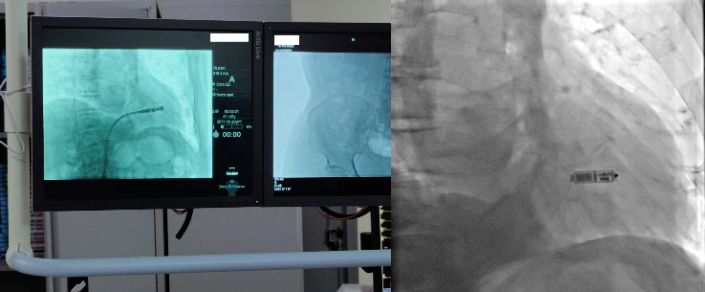

2022年11月16日,心血管内科三病区心脏介入团队在科主任孙林教授指导下,成功完成一台新一代双腔无导线起搏器植入术,通过右侧股静脉在患者心脏内“扎根”,让患者重获“心”生。

无导线起搏器是一种新兴的心脏起搏器,让“不开刀即可安装起搏器”的梦想成为现实。它身形小巧,只有胶囊大小,重仅2克。但却拥有超强的电池续航能力,寿命超过12年。同时兼容1.5T/3.0T核磁共振扫描,可满足患者之后疾病诊断需求。与传统心脏起搏器相比,双腔无导线起搏器体积减少93%,整个手术过程时间短,植入成功率高。可以保存心房、心室的顺序收缩功能,实现生理性起搏功能,开启了“无导线起搏新时代”。该技术的成功开展,是av线上 心血管内科三病区不断开展新技术、持续提升服务水平的生动注脚。未来,心血管内科将持续推进该项技术的普及,为更多患者的“心健康”保驾护航。